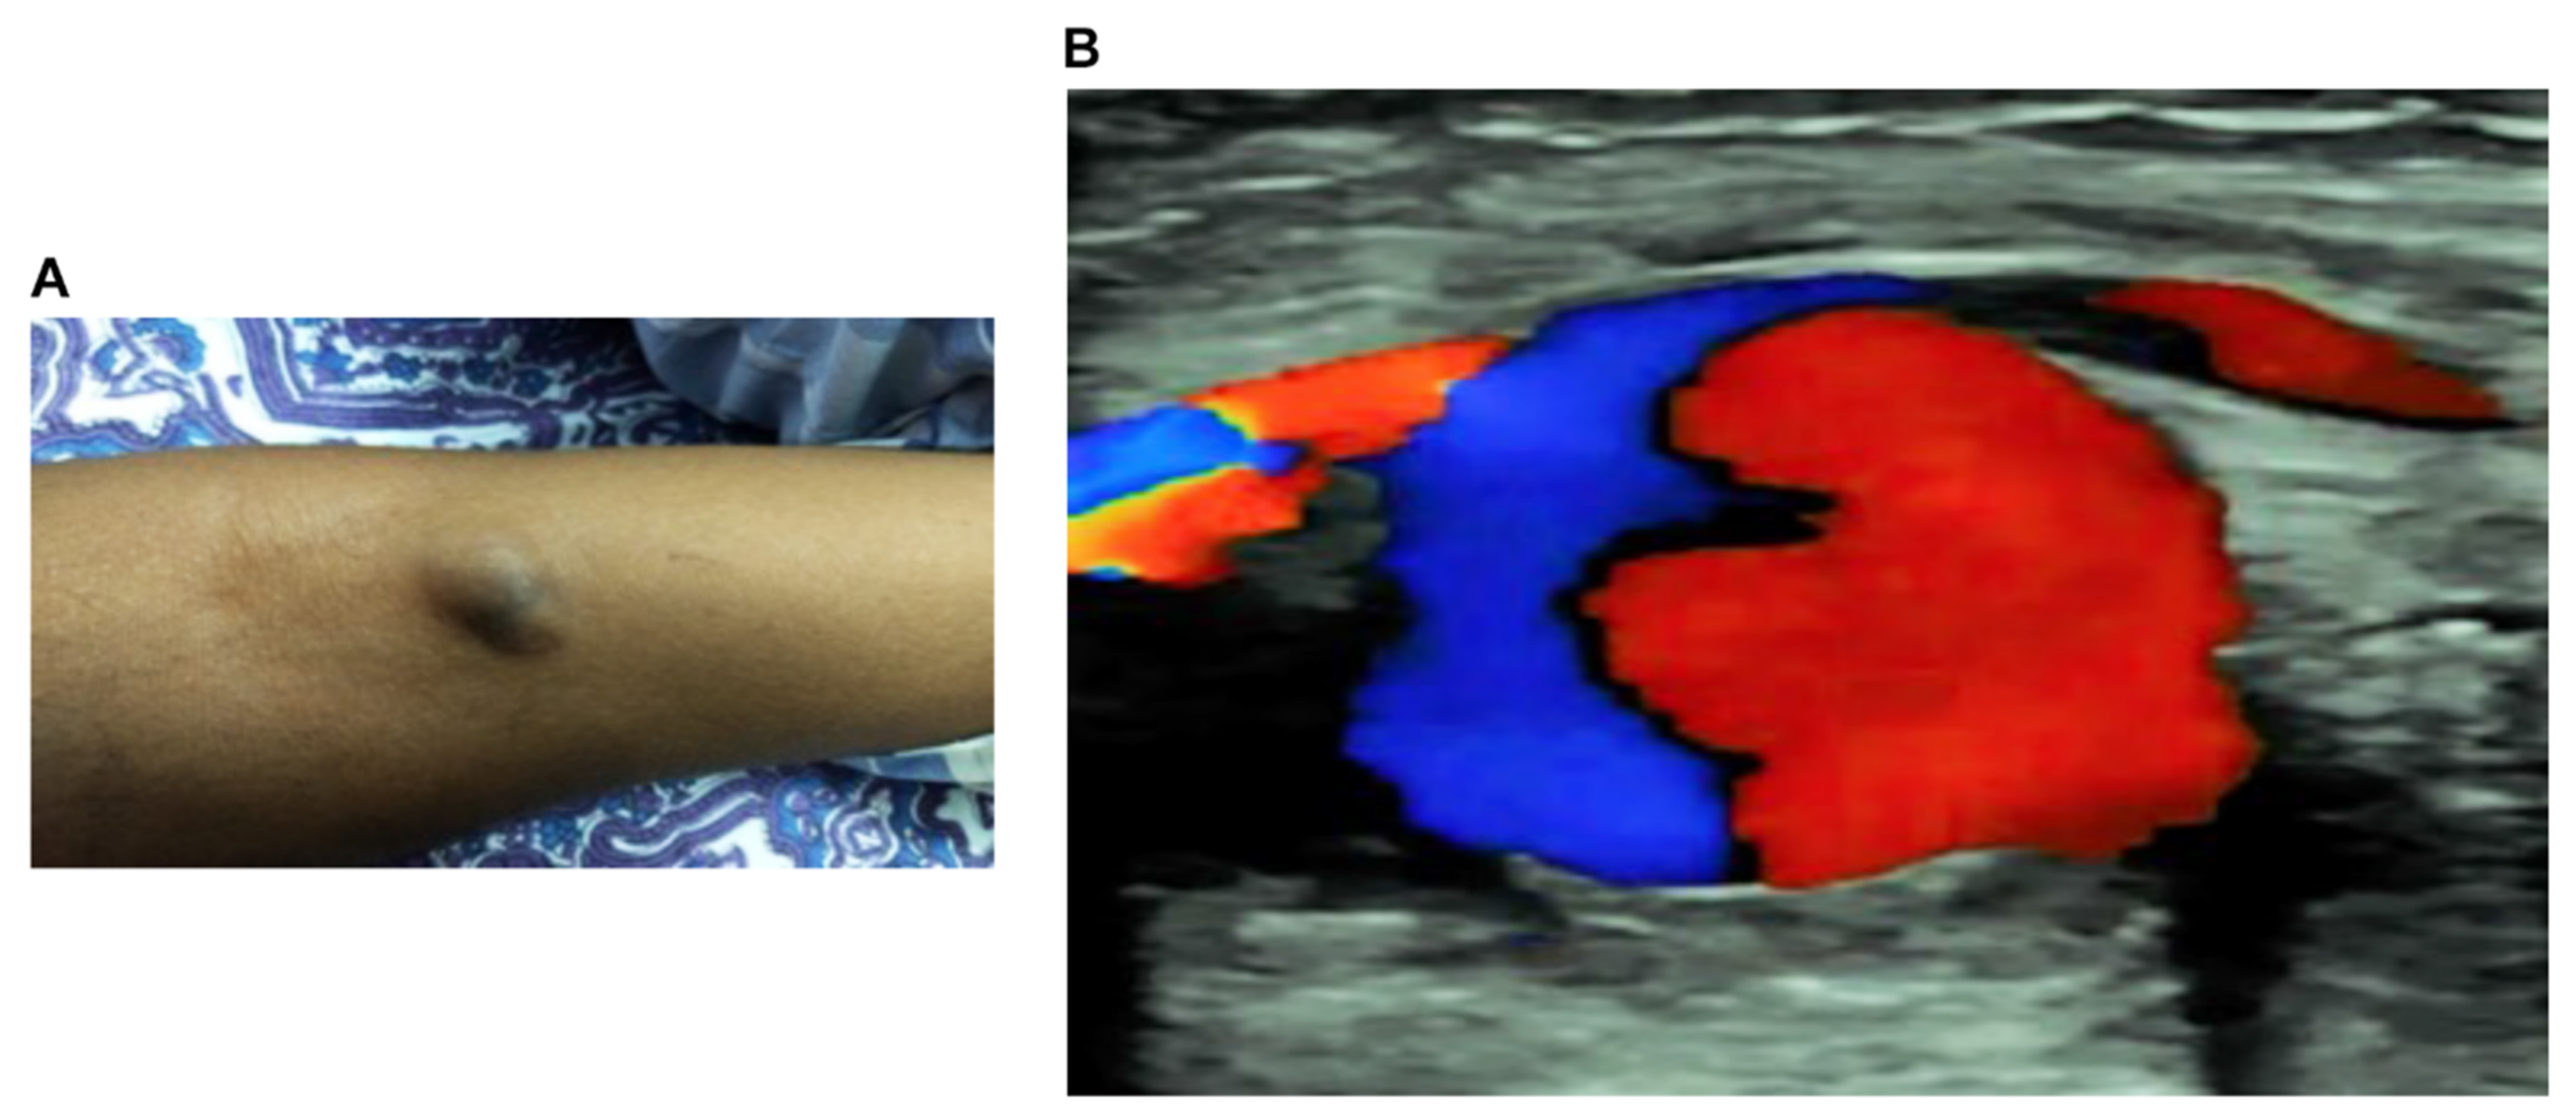

2.2. Ultrasound Diagnosis Confirms the PA in Ulnar Artery of Victims